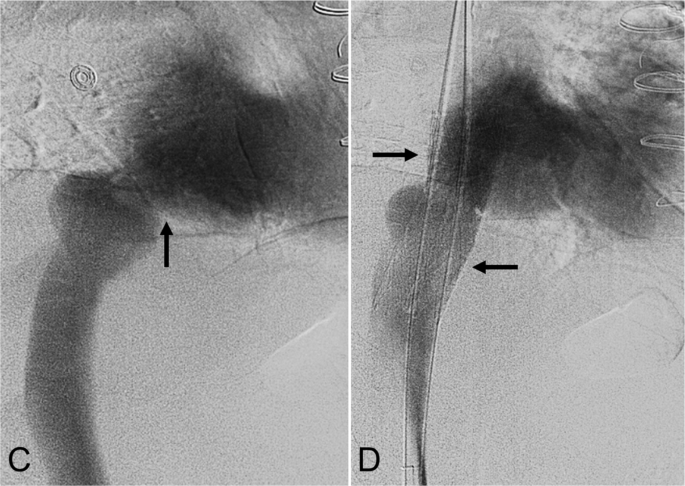

一名76岁的男性,在因非扩张型缺血性心肌病(ICM)接受OHT手术后4,756天,出现肝硬化、门脉高压和活动性呼吸困难。此次移植手术需要使用20毫米的Dacron移植物来延长腔静脉-心房吻合口。7天前的心脏导管检查显示初始压力差为11毫米汞柱。下腔静脉造影显示狭窄程度超过95%(图3E)。放置了一枚20毫米×120毫米的Abre支架,并扩张至16毫米。术后造影显示血流顺畅。IVUS和锥形束CT确认支架扩张效果良好(图3F)。最终腔静脉-心房压力差为2毫米汞柱。患者术后偶尔出现心悸,心电图显示窦性心律正常。随访影像显示支架位置稳定,症状在6天内消失。

一名76岁的男性,在因非扩张型缺血性心肌病接受OHT手术后4,756天,出现肝硬化、门脉高压和活动性呼吸困难。E 下腔静脉造影显示吻合口狭窄(黑色箭头)。F 重建后的造影显示20毫米×120毫米的Abre支架(黑色箭头)已放置到位,狭窄得到缓解